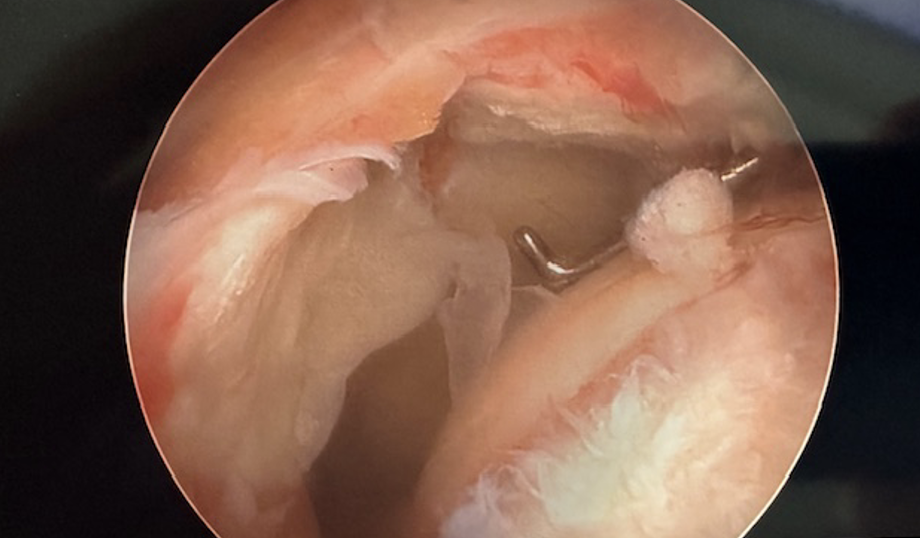

Arthroscopic picture of an Acute Rotator Cuff Repair - Before & After